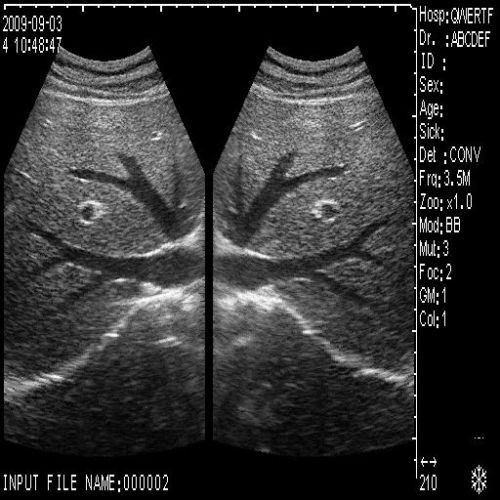

image: +3D High clear

Probe Function: 3.5MHZ convex, abdominal organs

High-Quality Imaging Capabilities

The Diagnostic Ultrasound Scanner stands out for its exceptional imaging capabilities. Utilizing advanced digital technology, it provides clear and precise images, essential for accurate diagnostics. This scanner is equipped with both convex and transvaginal probes, allowing healthcare professionals to perform a wide range of examinations. Because of this versatile functionality, it greatly enhances the diagnostic process in various medical fields.

This ultrasound machine is designed with the user in mind. Its intuitive interface simplifies operation, allowing even novice users to quickly become proficient. The compact design makes it easy to transport, which is especially beneficial in busy clinical settings. Additionally, the machine offers 3D imaging capabilities, enabling detailed visualization, which is crucial for effective patient assessments. Therefore, healthcare providers can rely on this scanner for both routine and specialized examinations.